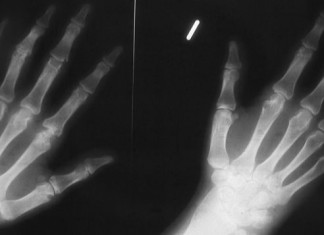

Restaurada en pacientes la proteína que falta en la distrofia muscular

Avances en el tratamiento de la distrofia muscular: Por primera vez, un equipo de investigación ha logrado restablecer una proteína de reparación que falta...